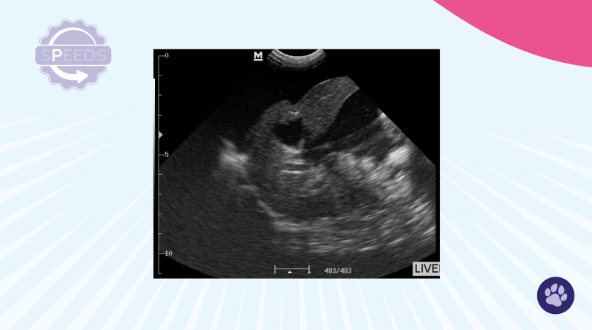

What Does Hepatomegaly Look Like?

When you're scanning in that near-field position (close to the stomach), reduce your depth to really focus on this area. You should be able to make a clear judgment:

- Is the liver rounded instead of sharp?

- Is it distorted in shape?

If yes to either, you're looking at hepatomegaly.